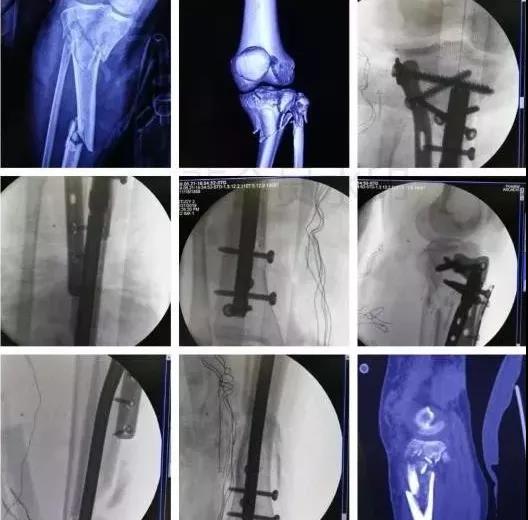

5)胫骨近端骨折(平台)

- 确定损伤机制,暴力损伤程度。

- 排除骨筋膜室综合征及血管,神经损伤。

- 高能量损伤,皮肤软组织条件差的,应延期手术。